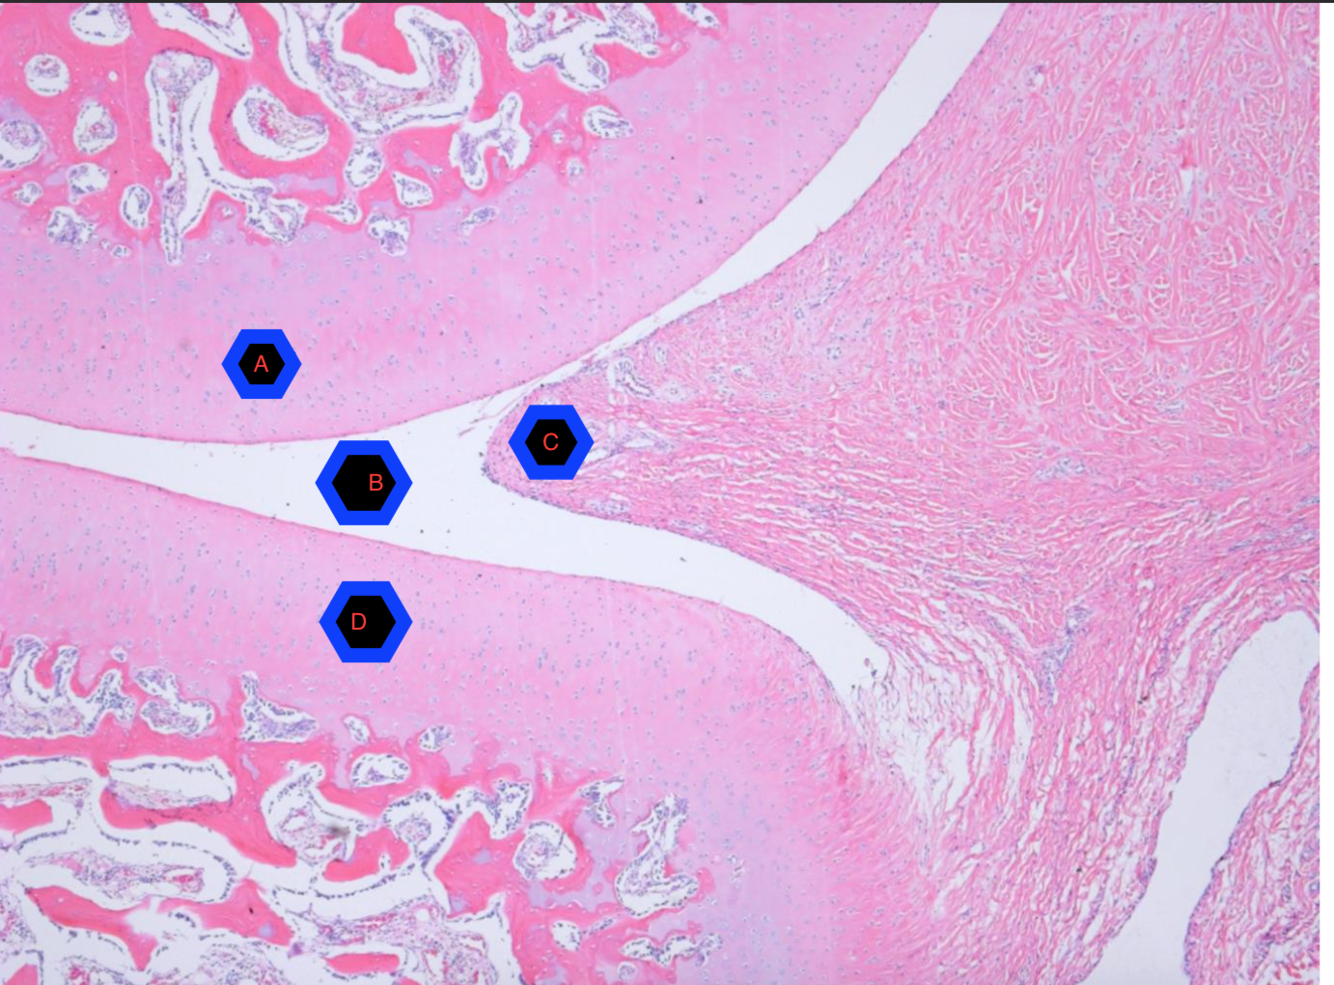

A/D) Articular cartilage B) Synovial cavity C) Synovial Joint Capsule

A/E) Synovial Capsule B) Joint Cavity C/D) Articular cartilage

A) Ligament B) Joint capsule C) Synovial lining D) Synovial cavity E/F) Articular cartilage G) Medullary trabecular bone H) Cortical Bone